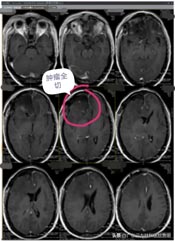

肿瘤体积巨大,占位明显,医院副院长、神经外五科主任鲁明和团队一起经过讨论,快速制定了安全且风险较小的手术方案,术中需要避开重要血管,尽最大可能全切除肿瘤。术前进行全脑血管造影,影像显示:前颅底异常染色,呈类圆形,肿瘤主要是由右侧脑膜中动脉前支、右侧眼动脉分支参与供血;决定先行肿瘤栓塞术,术后加压包扎送病人至手术室,行“前颅底巨大脑膜瘤切除术”。肿瘤周围血管丰富,已侵犯重要神经;导航准确定位,显微镜下见肿瘤起源于大脑镰及前颅底,阻断肿瘤血供后,先钨刀切除左侧额部部分肿瘤,再超吸切进行瘤内减压,最终镜下将肿瘤切除干净。

术后第二天,林阿姨便返回普通病房,神志清楚,无功能障碍,术前担心的并发症都没有发生。在医生护士及家人的精心照顾下,半个月后,林阿姨就步行出院了。